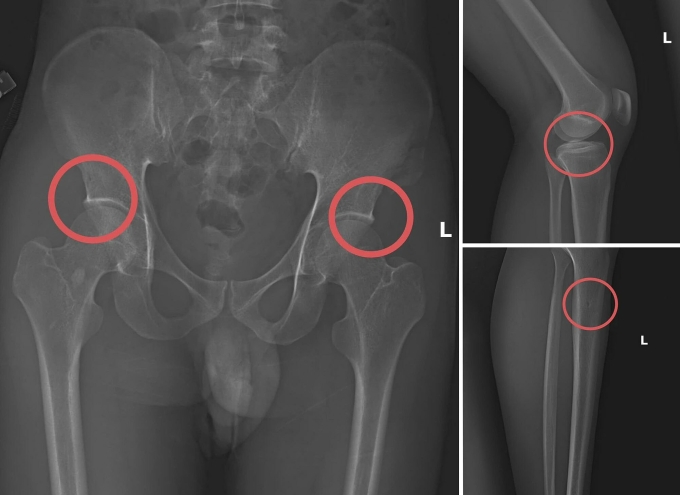

Châu trực tiếp thực hiện hành vi tiêm thuốc mê rồi dùng kim tiêm, búa đinh để tác động vào xương người mua bảo hiểm. Sau khi can thiệp đã tạo nên các vết nứt, vỡ xương giống hệt bị tai nạn thật. Tạo thương tích xong, anh ta tiếp tục hướng dẫn đồng phạm dựng hiện trường giả như điện giật ngã, trượt chân ngã suối nhằm hợp thức hóa bệnh án và hoàn thiện hồ sơ yêu cầu chi trả.

Công an Phú Thọ đánh giá, đường dây này hoạt động có tổ chức, tinh vi nhằm qua mặt cảnh sát. Thủ đoạn “tàn nhẫn, vô nhân tính, coi thường sức khỏe, tính mạng của người tham gia”. Chúng đã lên kế hoạch, tính toán kỹ để gây thương tích đúng vị trí có mức chi trả cao, khiến các công ty bảo hiểm khó phát hiện dấu hiệu gian dối.